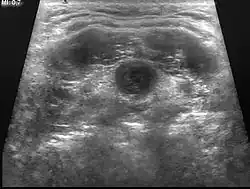

Quiste tirogloso

En medicina, un quiste tirogloso es un quiste fibroso que se forma de manera persistente en el conducto tirogloso, usualmente el medio del cuello, doloroso a la palpación, en especial si llega a infectarse. Puede causar dificultades para respirar, para tragar[1] y/o malestar abdominal, especialmente si la masa se torna grande.